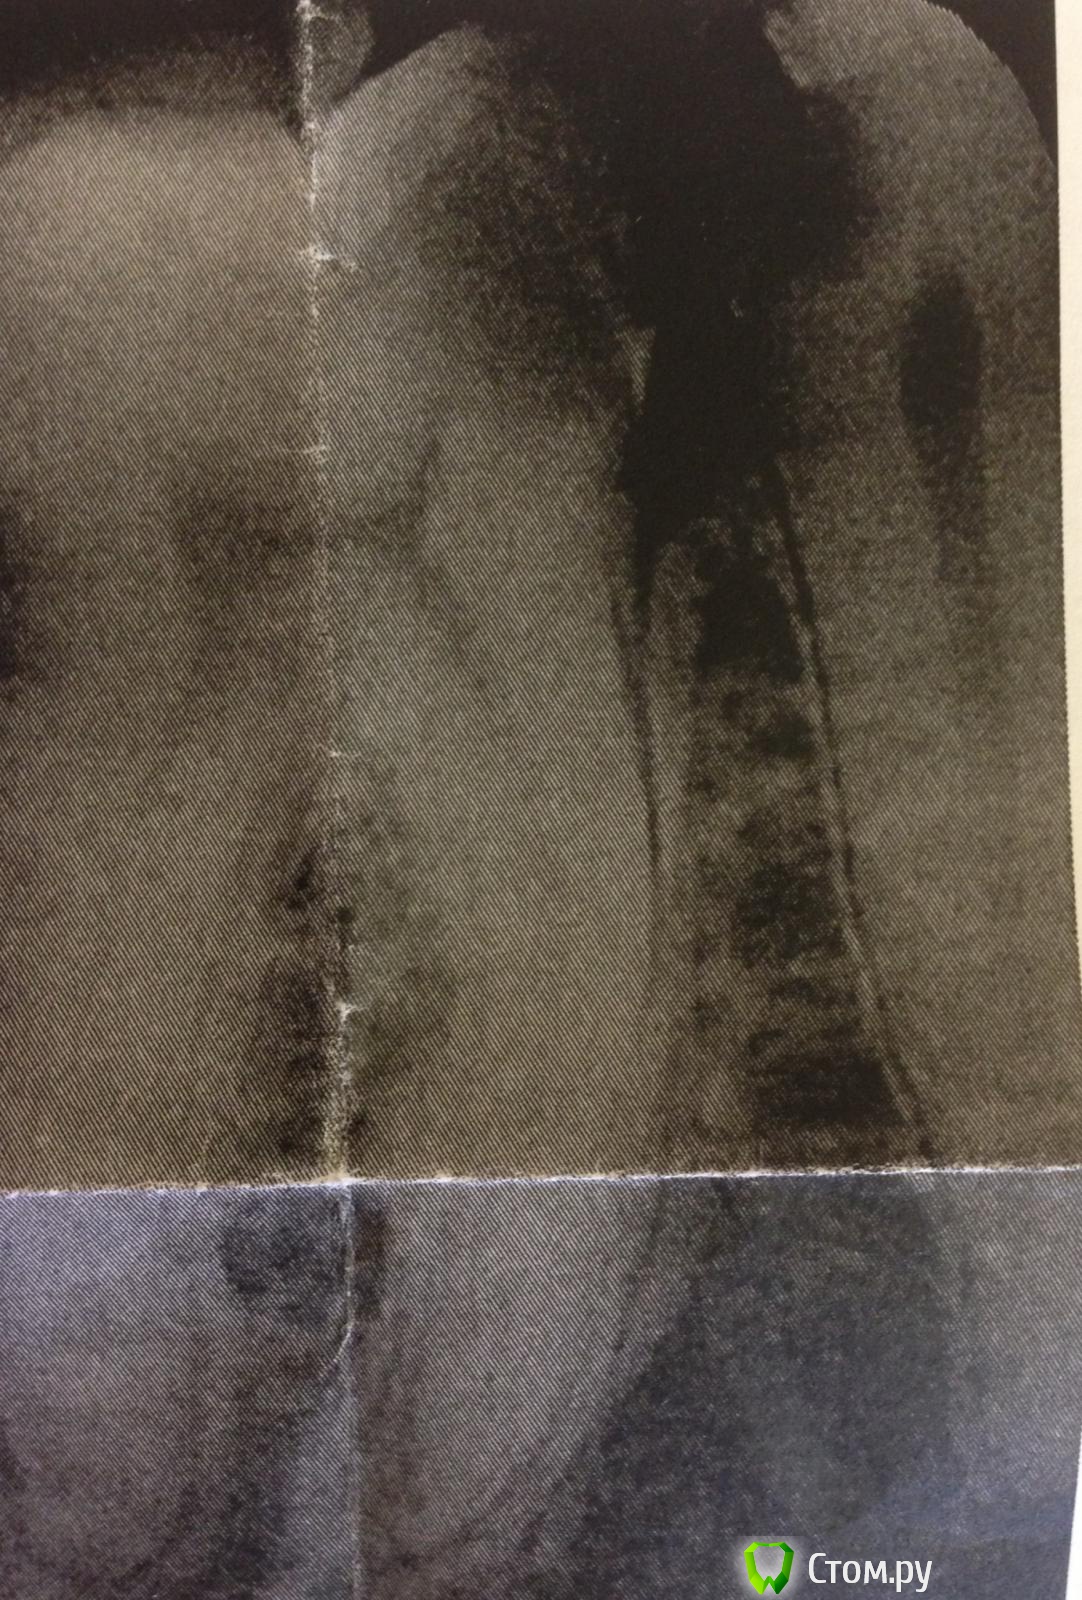

SSTi Опубликовано 28 июня, 2014 Автор Поделиться Опубликовано 28 июня, 2014 37 выпала пломба- вскрытая точка - пульпит. 2 вопроса. 1- как вы предотвращаете выход силера за верхушку при изначально широком апикальном отверстии?( как здесь в дистальном)2. - нет подозрений по снимку на 3й канал медиальный??мед устья были смещены сильно щечно. Расстояние между ними 1-1.5 мм. Были скрыты под дентиклем. Меня посещают мысли, что это мщ и мм. А не мщ и мя. Хотя от устья дистального сулькус шел и раздваивался только в направлении этих двух. Второй снимок - под углом. Датчик медиально, трубка дистально. Ссылка на комментарий